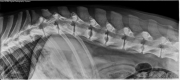

2 year old male neutered German Shepherd. Polyuria, polydipsia, and reluctance to jump on bed. What is your radiographic diagnosis?

R LAT Spine

On lateral survey radiographs of the spine, there are multiple intervertebral disc spaces affected by vertebral endplate lysis with surrounding sclerosis. The largest of these appear to be C3-4 and L1-2. Multiple additional thoracic and lumbar intervertebral disc spaces are affected.

• Discospondylitis (bacterial, fungal)

• Discospondylitis and pyelonephritis caused by disseminated Aspergillosis

• An aortic thrombus was also discovered on abdominal ultrasound

German Shepherd dogs are predisposed to disseminated Aspergillosis.